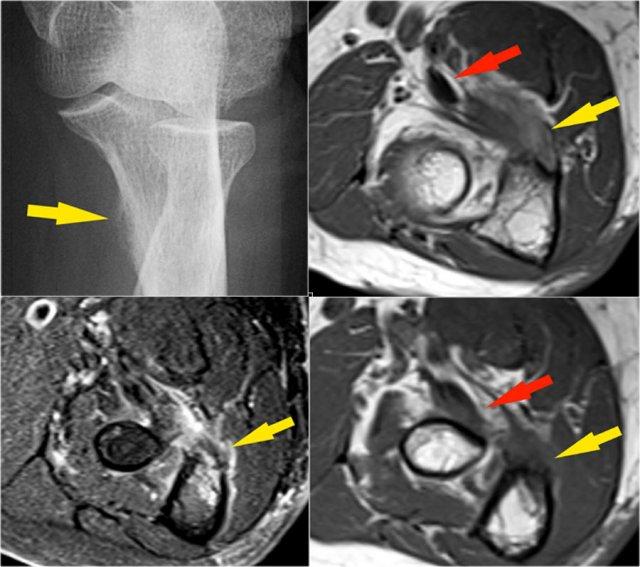

Elbow dislocation

Đây là hình ảnh chụp X-quang tư thế nghiêng của khuỷu tay một bệnh nhân bị ngã chống tay duỗi thẳng.

Hình ảnh X-quang cho thấy tràn dịch khớp (mũi tên đỏ) và gãy mỏm vẹt (mũi tên vàng).

Continue with the MR-images.

Đây là hình ảnh MRI.

Hãy xem các hình ảnh và sau đó tiếp tục đọc…

Coronal view:

- Dây chằng bên ngoài bị bóc tách hoàn toàn (mũi tên vàng).

- radial head is subluxed.

- phù tủy xương của mỏm vẹt do gãy xương (mũi tên đỏ).

Sagittal view:

- Chỏm xương quay bị bán trật nhẹ ra phía sau (mũi tên vàng).

- Large effusion and capsular disruption posteriorly.

- Đụng dập mặt sau của chỏm con do va chạm với mỏm vẹt (mũi tên đỏ).

All these signs are the result of a posterior dislocation.

Những hình ảnh này của một nam giới 23 tuổi bị ngã chống tay khi đang trượt ván hai tuần trước.

Khi khám lâm sàng, ghi nhận giảm biên độ vận động khớp khuỷu và đau khi ấn dọc theo mặt ngoài.

First study the images, then continue reading…

Cấu trúc nào nằm phía sau chỏm quay trên hình ảnh cắt ngang?

- Một lần nữa, hình ảnh đặc trưng của phù tủy xương thường gặp trong trật khớp khuỷu tay ra sau với vết dập ở phía trước của chỏm xương quay (mũi tên đỏ) và ở phía sau của chỏm con xương cánh tay.

- Chỏm quay phải đã va chạm vào phần sau của chỏm con xương cánh tay.

Cấu trúc phía sau chỏm quay là dây chằng vòng.

Nó không đều và dày lên do hậu quả của trật khớp ra sau.